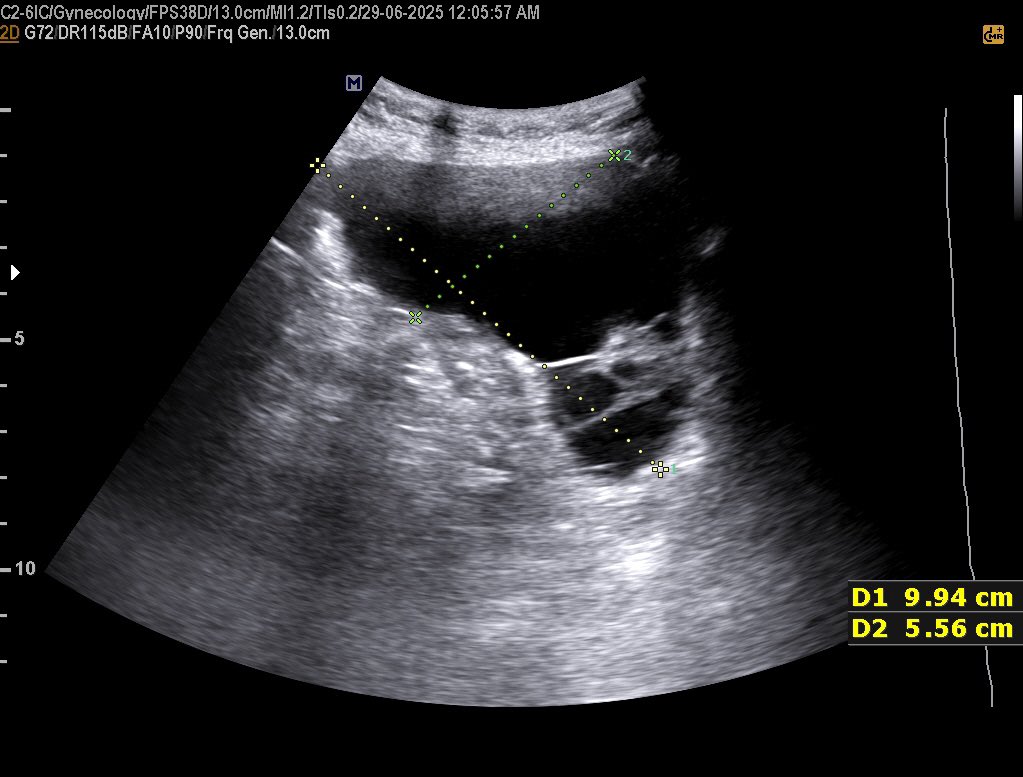

𝗖𝗘𝗥𝗩𝗜𝗖𝗔𝗟 𝗟𝗘𝗡𝗚𝗧𝗛 𝗜𝗡 𝗨𝗟𝗧𝗥𝗔𝗦𝗢𝗨𝗡𝗗 Normal Cervical Length : ≥25 mm Risk starts : <25 mm Serious risk : <15 mm #EchoTech

𝗖𝗘𝗥𝗩𝗜𝗖𝗔𝗟 𝗟𝗘𝗡𝗚𝗧𝗛 𝗜𝗡 𝗨𝗟𝗧𝗥𝗔𝗦𝗢𝗨𝗡𝗗 Normal Cervical Length : ≥25 mm Risk starts : <25 mm Serious risk : <15 mm #EchoTech

𝗖𝗘𝗥𝗩𝗜𝗖𝗔𝗟 𝗟𝗘𝗡𝗚𝗧𝗛 𝗜𝗡 𝗨𝗟𝗧𝗥𝗔𝗦𝗢𝗨𝗡𝗗 Normal Cervical Length : ≥25 mm Risk starts : <25 mm Serious risk : <15 mm #EchoTech